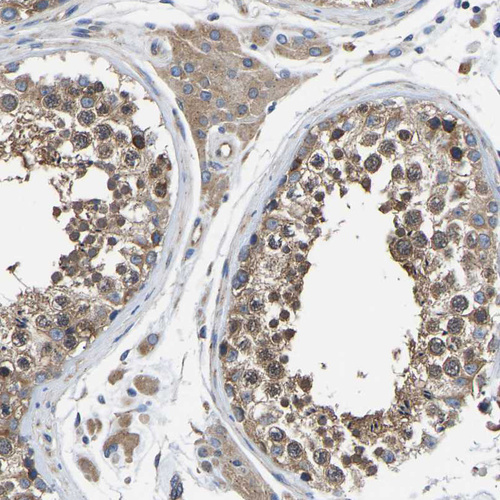

Immunohistochemical staining of human placenta shows strong cytoplasmic positivity in trophoblastic cells.